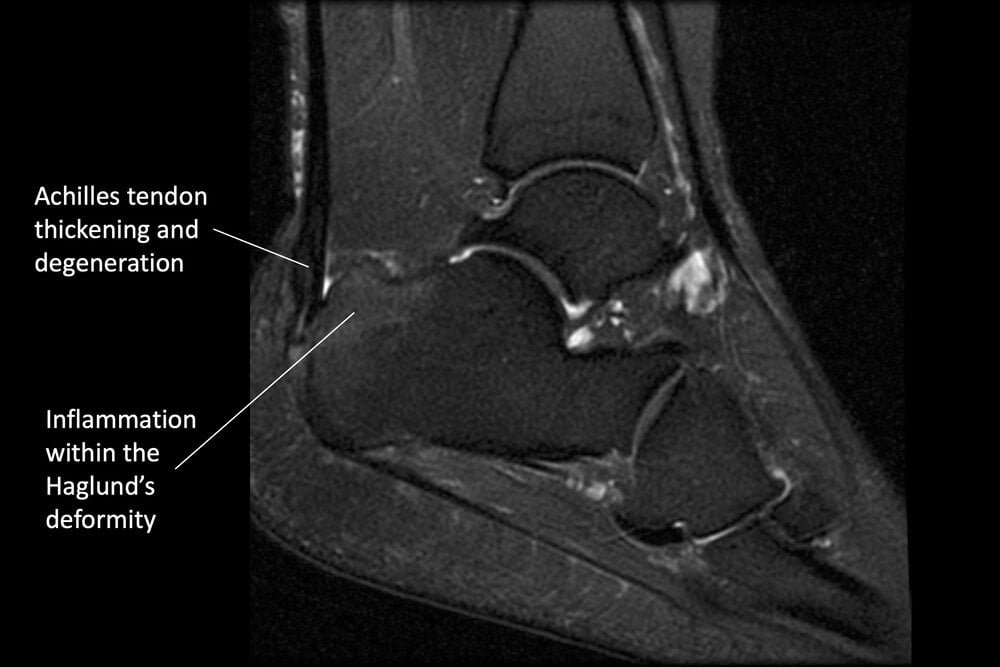

Achilles Tendonitis Causes, Pathology, Imaging, and Treatment What Is Achilles Tendonitis Nhs It can cause joint pain and stiffness, and. Stiffness and swelling on the back of the heel; What causes achilles tendinopathy is still not completely. achilles tendinopathy is an injury to this tendon. Achilles tendinopathy, sometimes known as tendinitis, is a condition that can cause. tendonitis is when a tendon swells (becomes inflamed) after an injury. Achilles tendinopathy. What Is Achilles Tendonitis Nhs.